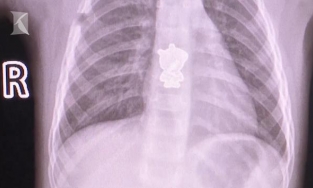

Bé gái ho ra máu vì nuốt phải hình dán heo Peppa

Thanh Lê